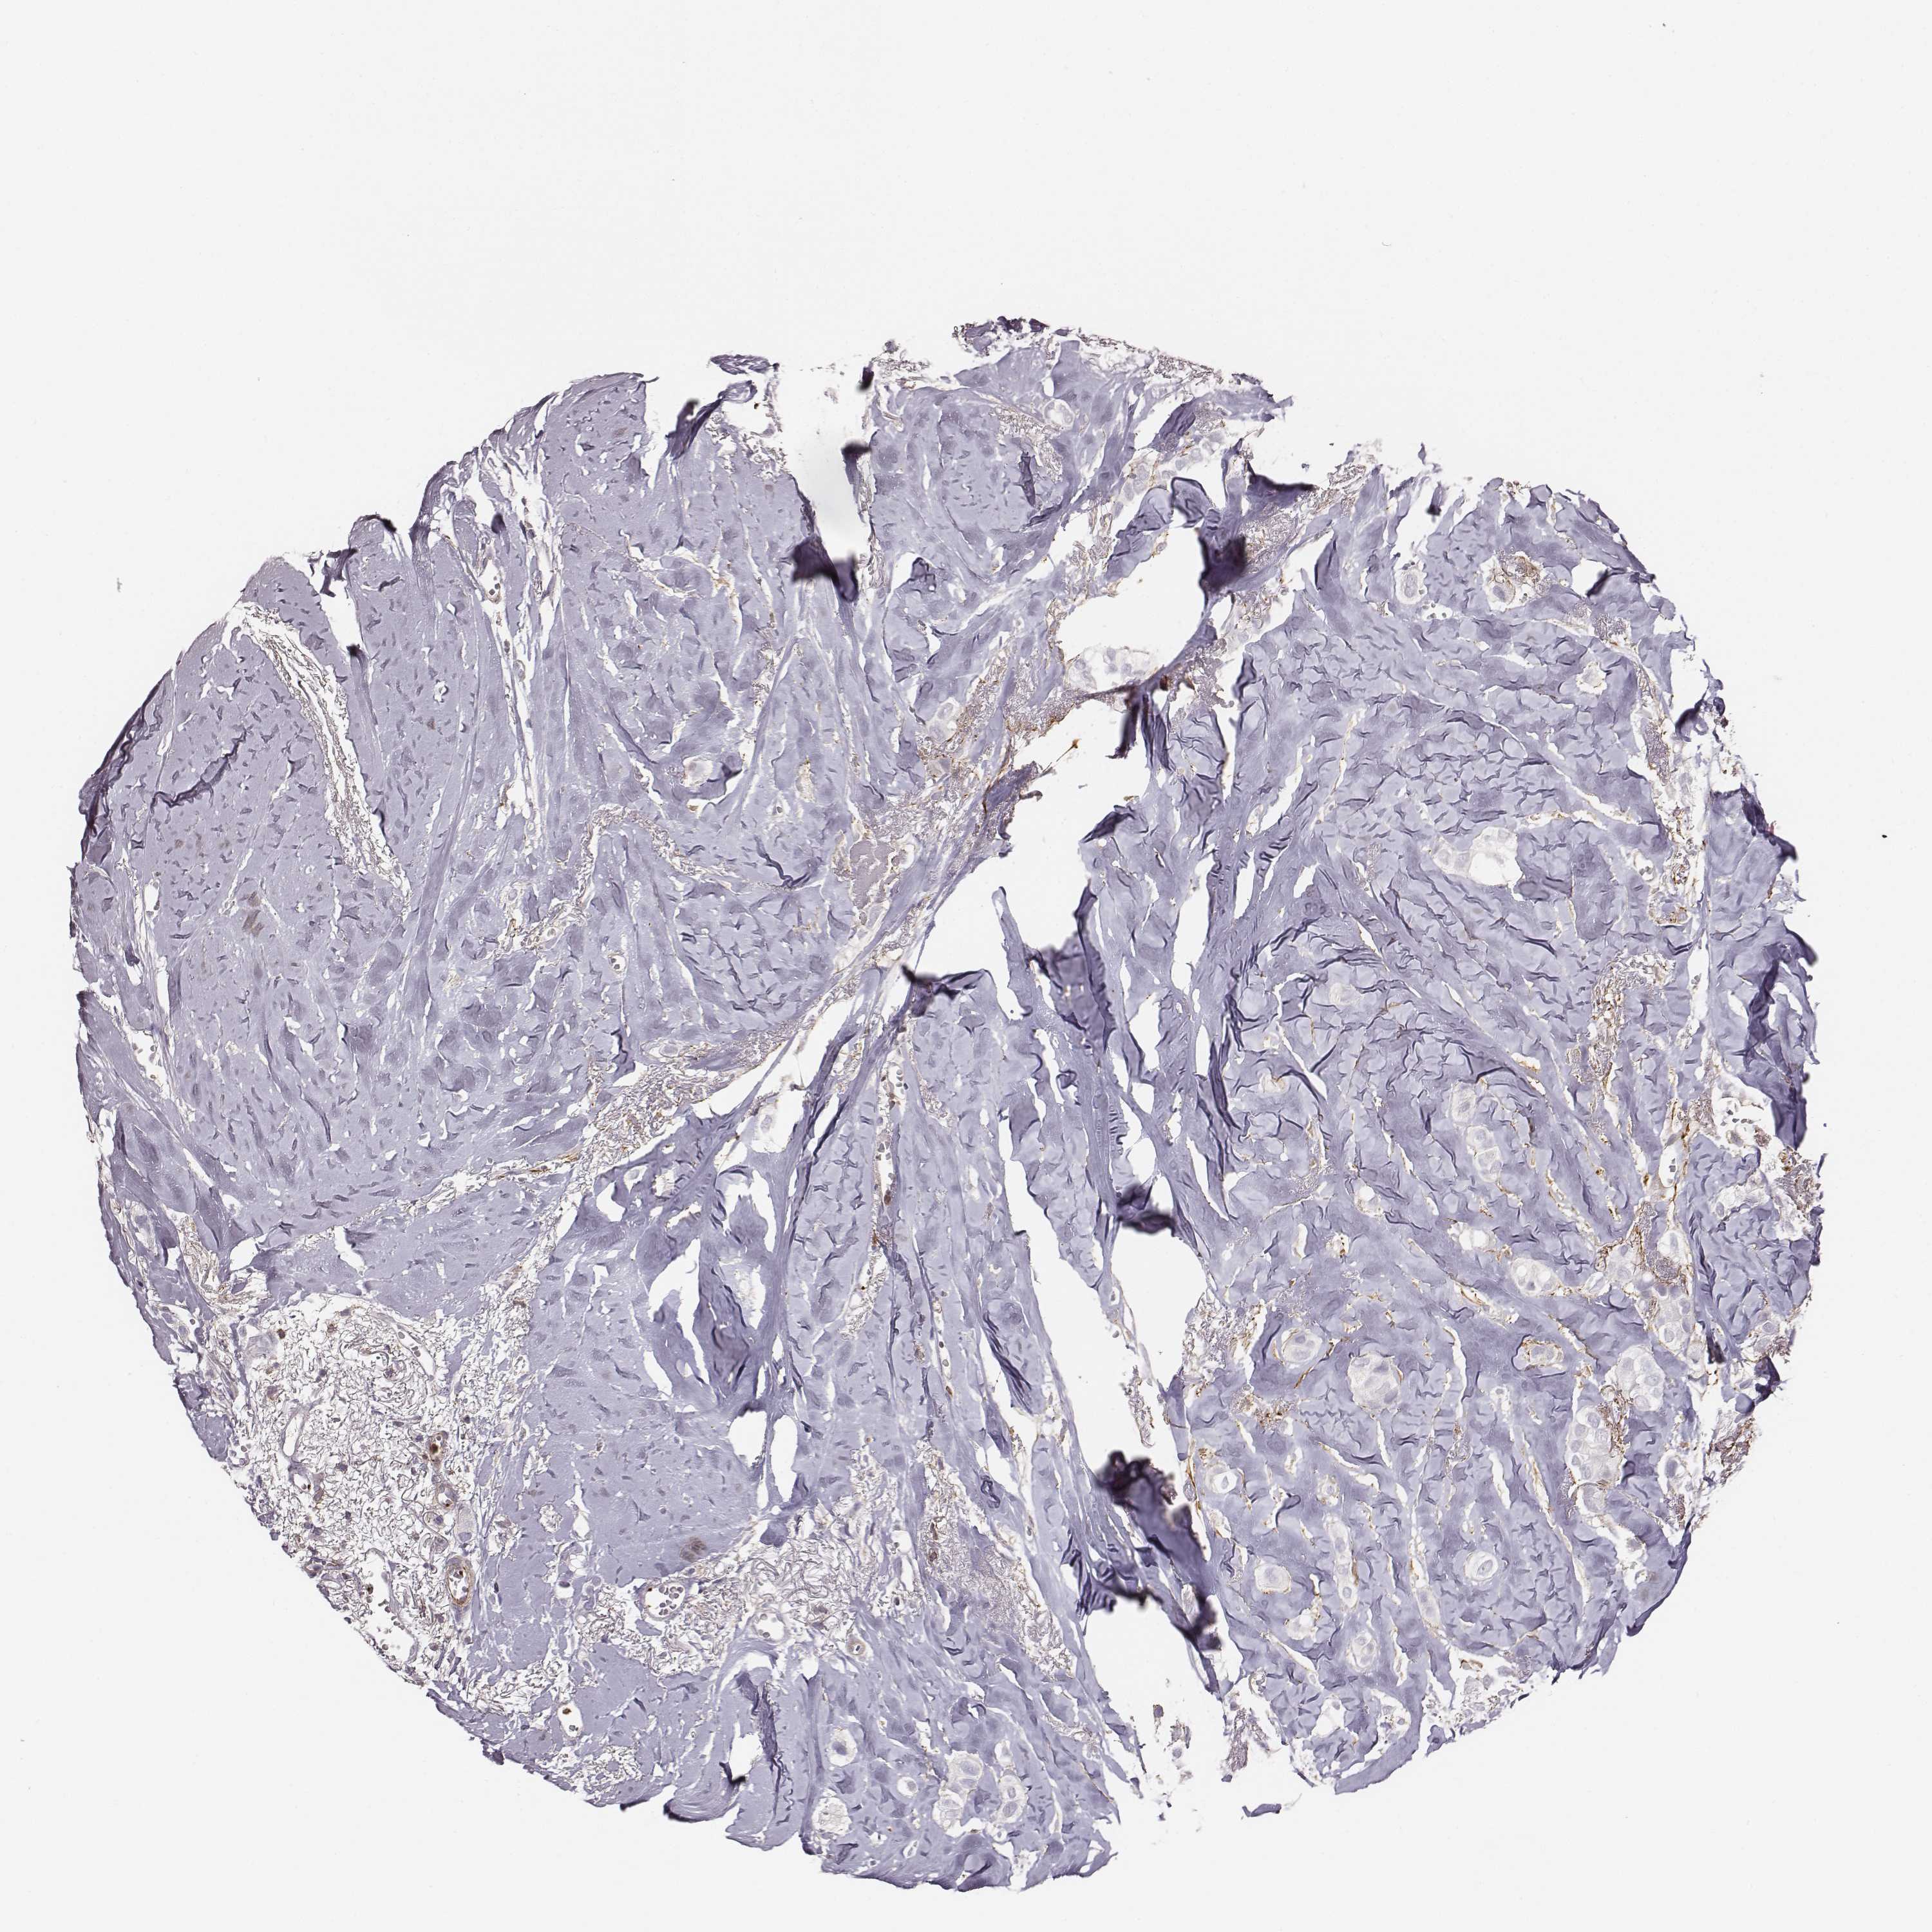

CANCER BREAST CANCER Show tissue menu

BRCA TCGA BRCA VALIDATION PROTEIN EXPRESSION